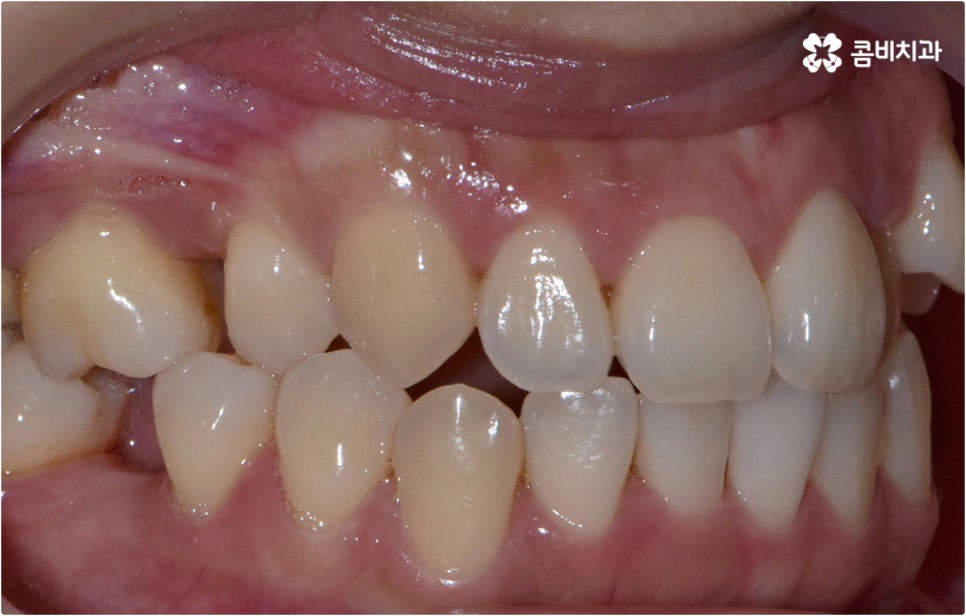

치아설측교정 은 겉으로 장치가 드러나지 않아서 가까운 사람이 아니면 교정 치료를 진행한다는 것을 알아차리기 힘들 정도로 심미성이 뛰어난데, 이러한 장점을 가지고 있는 반면 혀가 아랫니 쪽 장치에 닿다 보니 발음이 불분명해지거나 이물감 및 통증을 느끼는 경우가 있어 주의할 필요가 있어요.

이런 때는 치아설측교정 대신 비교적 잘 보이는 윗니는 설측으로 진행하고, 입술에 가려 잘 보이지 않는 아랫니는 순측(입술쪽)으로 진행하는 콤비교정을 이용하면 발음, 이물감, 통증 문제를 해결할 수 있습니다. 콤비교정 시 치아 겉면에 부착하는 아랫니 브라켓의 경우 치아와 색상이 비슷한 세라믹 재질을 이용하기 때문에 심미성도 크게 떨어지지 않으며 치아설측교정 으로 전체를 진행하는 것 보다 비용적인 부담도 줄여주므로 설측 교정 치료를 생각하시는 분들이라면 콤비교정 역시 함께 알아보시길 권유드리고 있어요.

이와 같이 치아설측교정 과 콤비교정은 브라켓을 치아 안쪽으로 붙여서 치료하는 방식이기 때문에 굉장히 고난도의 복잡한 교정 치료라고 할 수 있습니다. 교정에 대한 높은 이해도와 해부학적으로 뛰어난 노하우, 풍부한 경험을 통해 축적한 세심한 기술력을 갖추고 있는 의료진에게 치료를 맡기는 것이 중요하며 정밀 디지털 검진 장비를 통한 정확한 검사 결과를 바탕으로 무리하지 않게 진행하실 필요가 있어요. 또한 양치질을 할 때 음식물 제거가 쉽지 않으므로 환자분들 본인이 평상시 신경써서 닦아주시는 것은 물론 꼼꼼한 케어시스템을 통해 주기적으로 관리해 주는 치과에서 교정 치료 및 사후 유지 관리까지 철저하게 받아보시길 권유드리고 있습니다.